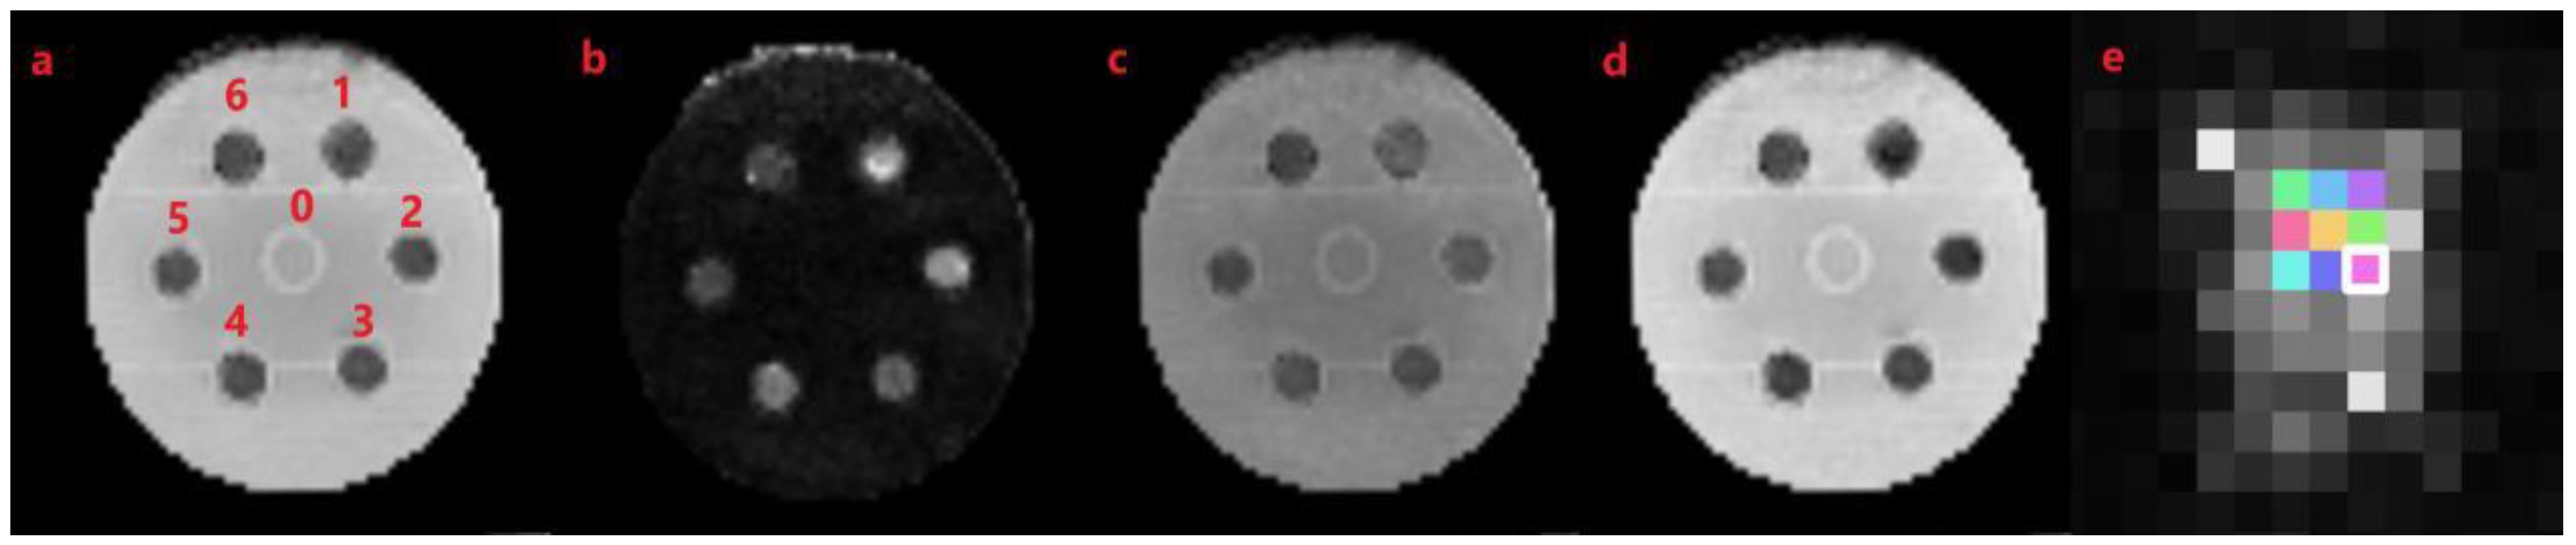

3.4. MR Imaging of Spinal Cord-Mimicking Phantoms